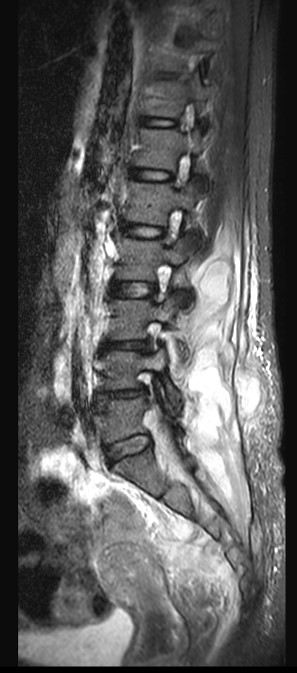

Rozsáhlý absces paravertebrálních svalů páteře zasahující do páteřního kanálu v bederní oblasti.

MRI s/ bez kontrastu je zlatým standardem – ukáže zánět, otok v okolí páteřního kanálu, abscesy a rozlišuje je od jiných onemocnění. RTG může ukázat zúžení disku nebo eroze kostí, ale jen v pozdějších stádiích (2+ týdny); CT je užitečné v pozdějších stadiích pro detekci kostních změn, kontrolu deformit nebo plánování biopsie.